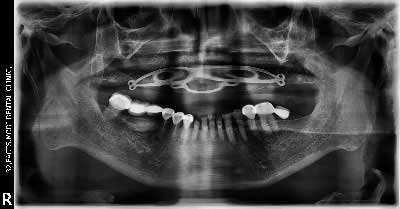

(26) Implant Placement

When Patient Came To Us

After 1 Week of Implant Placement

After 1 Year of Implant Placement

Patient aged 69 years with no significant medical history reported to the clinic with chief complaint of missing teeth and discomfort in chewing.Dental implants were placed for the upper jaw followed by immediate denture and final prosthesis were fixed after 4 months.